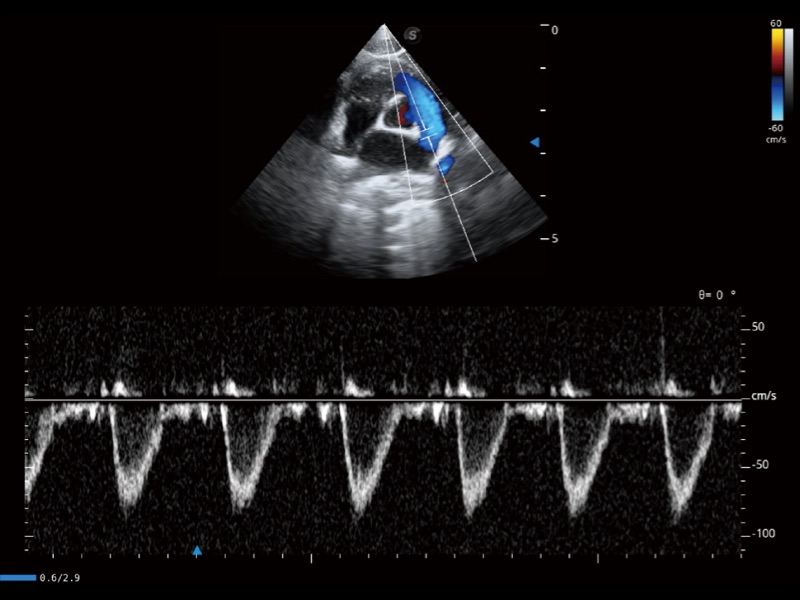

通过360度任意调节3条M型取样线,在同一心动周期上观察心脏不同位置的运动曲线,得到准确的心功能测量数据,有效评估心肌运动及左心室功能。

通过创新的 Matrix E自适应滤波器和超长时间域算法,极大提升超低速微细血流的检出能力,同时更精准地滤除软组织和噪声信号,为兽用医生提供以往无法通过常规血流获得的疾病诊断信息。

通过色彩血流和实时宽景相结合,可观察到完整的静脉或动脉的血流,方便医生检查。实时扫查过程中,如有任何操作失误也可以很容易地进行回扫擦除,而不会中断扫查。